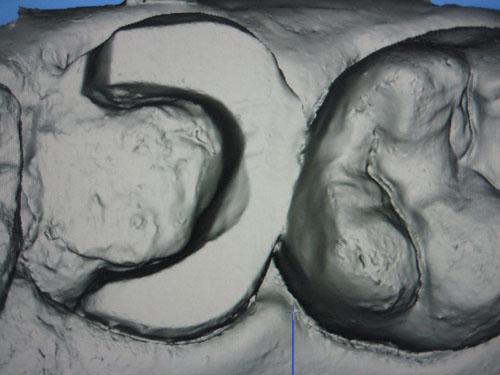

Dent 17 : Traitement endodontique et préparation pour Endocouronne effectées

3 murs ont été conservés (épaisseurs de 3 mm) et la limite est à ce niveau largement supra gingivale sauf en distal de la préparation mais cela ne gène en rien la saisie opto-électronique avec la caméra 3D (tant qu'il n'y a pas de saignement...)

Image 3D sur écran après empreinte optique au CEREC AC (Blue Cam)